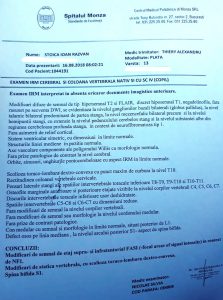

Răzvan Ioan Stoica are o curbură a coloanei vertebrale de 37 grade, iar aceasta se accentuează pe măsura trecerii timpului. Pentru ca lucrurile să nu se agraveze, el are nevoie cât mai urgent de o operație.

Răzvan a fost diagnosticat cu această boală de la vârsta de 4 ani și a purtat permanent un corset. Lucrurile s-au agravat însă, iar acum se impune intervenția chirurgicală.